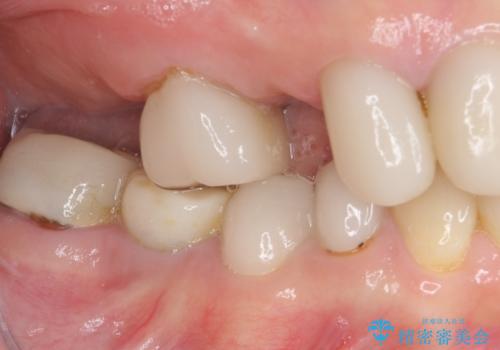

- 虫歯や歯の欠損を放置していることを気にして来院された患者様です。

下顎には抜歯が必要な歯があったため、抜歯後に治癒を待ち、上顎とともにオールセラミックブリッジにて補綴治療を行うこととしました。

治療開始の日に欠損部も含めて仮歯が装着され、今までの不具合や不快感があっという間に改善されました。

抜歯部位の治癒を待つために時間がかかりましたが、来院回数は数回で済み、患者様には大変満足していただきました。